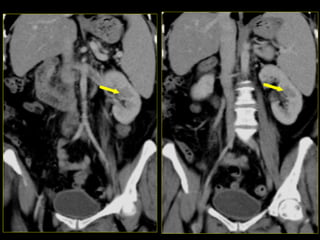

Caso # 2 ♀ , 6ta década de la vida  Estudio de TC para seguimiento y evaluación  de quistes renales.  Se realiza estudio con medio de contraste endovenoso, mostrándose la fase venosa, con cortes axiales y con reconstrucciones multiplanares (RMP) coronales.

Hallazgos Caso #2: Área hipodensa triangular en polo superior del riñón izquierdo, en relación con proceso inflamatorio lobar renal.